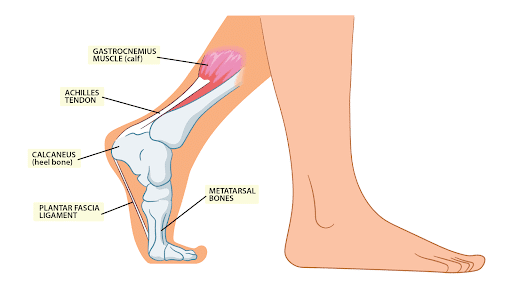

Burning feeling in achilles tendon clearance